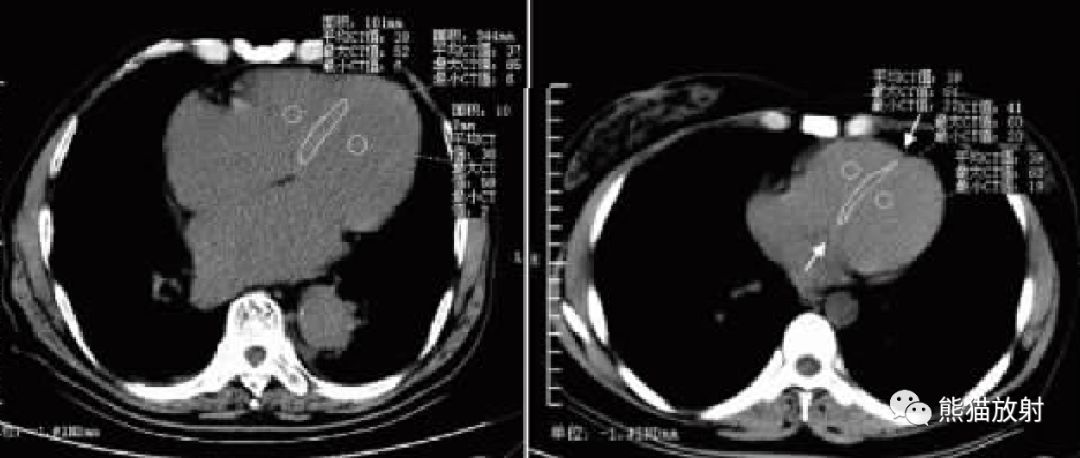

心室的CT密度与血液中Hb的浓度呈密切的正相关,而室间隔由心肌纤维组织构成,在排除心内膜疾病的情况下,其密度较少发生改变。

在胸部CT平扫图像上如果可以分辨出室间隔则提示有严重贫血的存在。

贫血程度与室隔差值存在相关性,血液Hb浓度的减低程度越严重,室间隔征越明显,室隔差值越大。

CT平扫诊断贫血的最佳定量方法是左心室和室间隔之间的差值。

在选择ROI 时尽量选择靠近室间隔的位置,减少乳头肌的影响。

↑ 重度贫血、中度贫血

↑ 轻度贫血、正常人